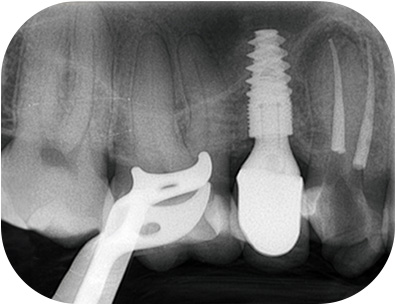

prémolaire, le composite présente une étanchéité insuffisanteFig. 01 : Ie composite présente une étanchéité insuffisante, notamment avec la reprise

d’une lésion carieuse en distal.

prémolaire, la LIPOE Fig. 02 : la LIPOE est centrée sur la racine

palatine et le canal est clairement

identifiable au CBCT.